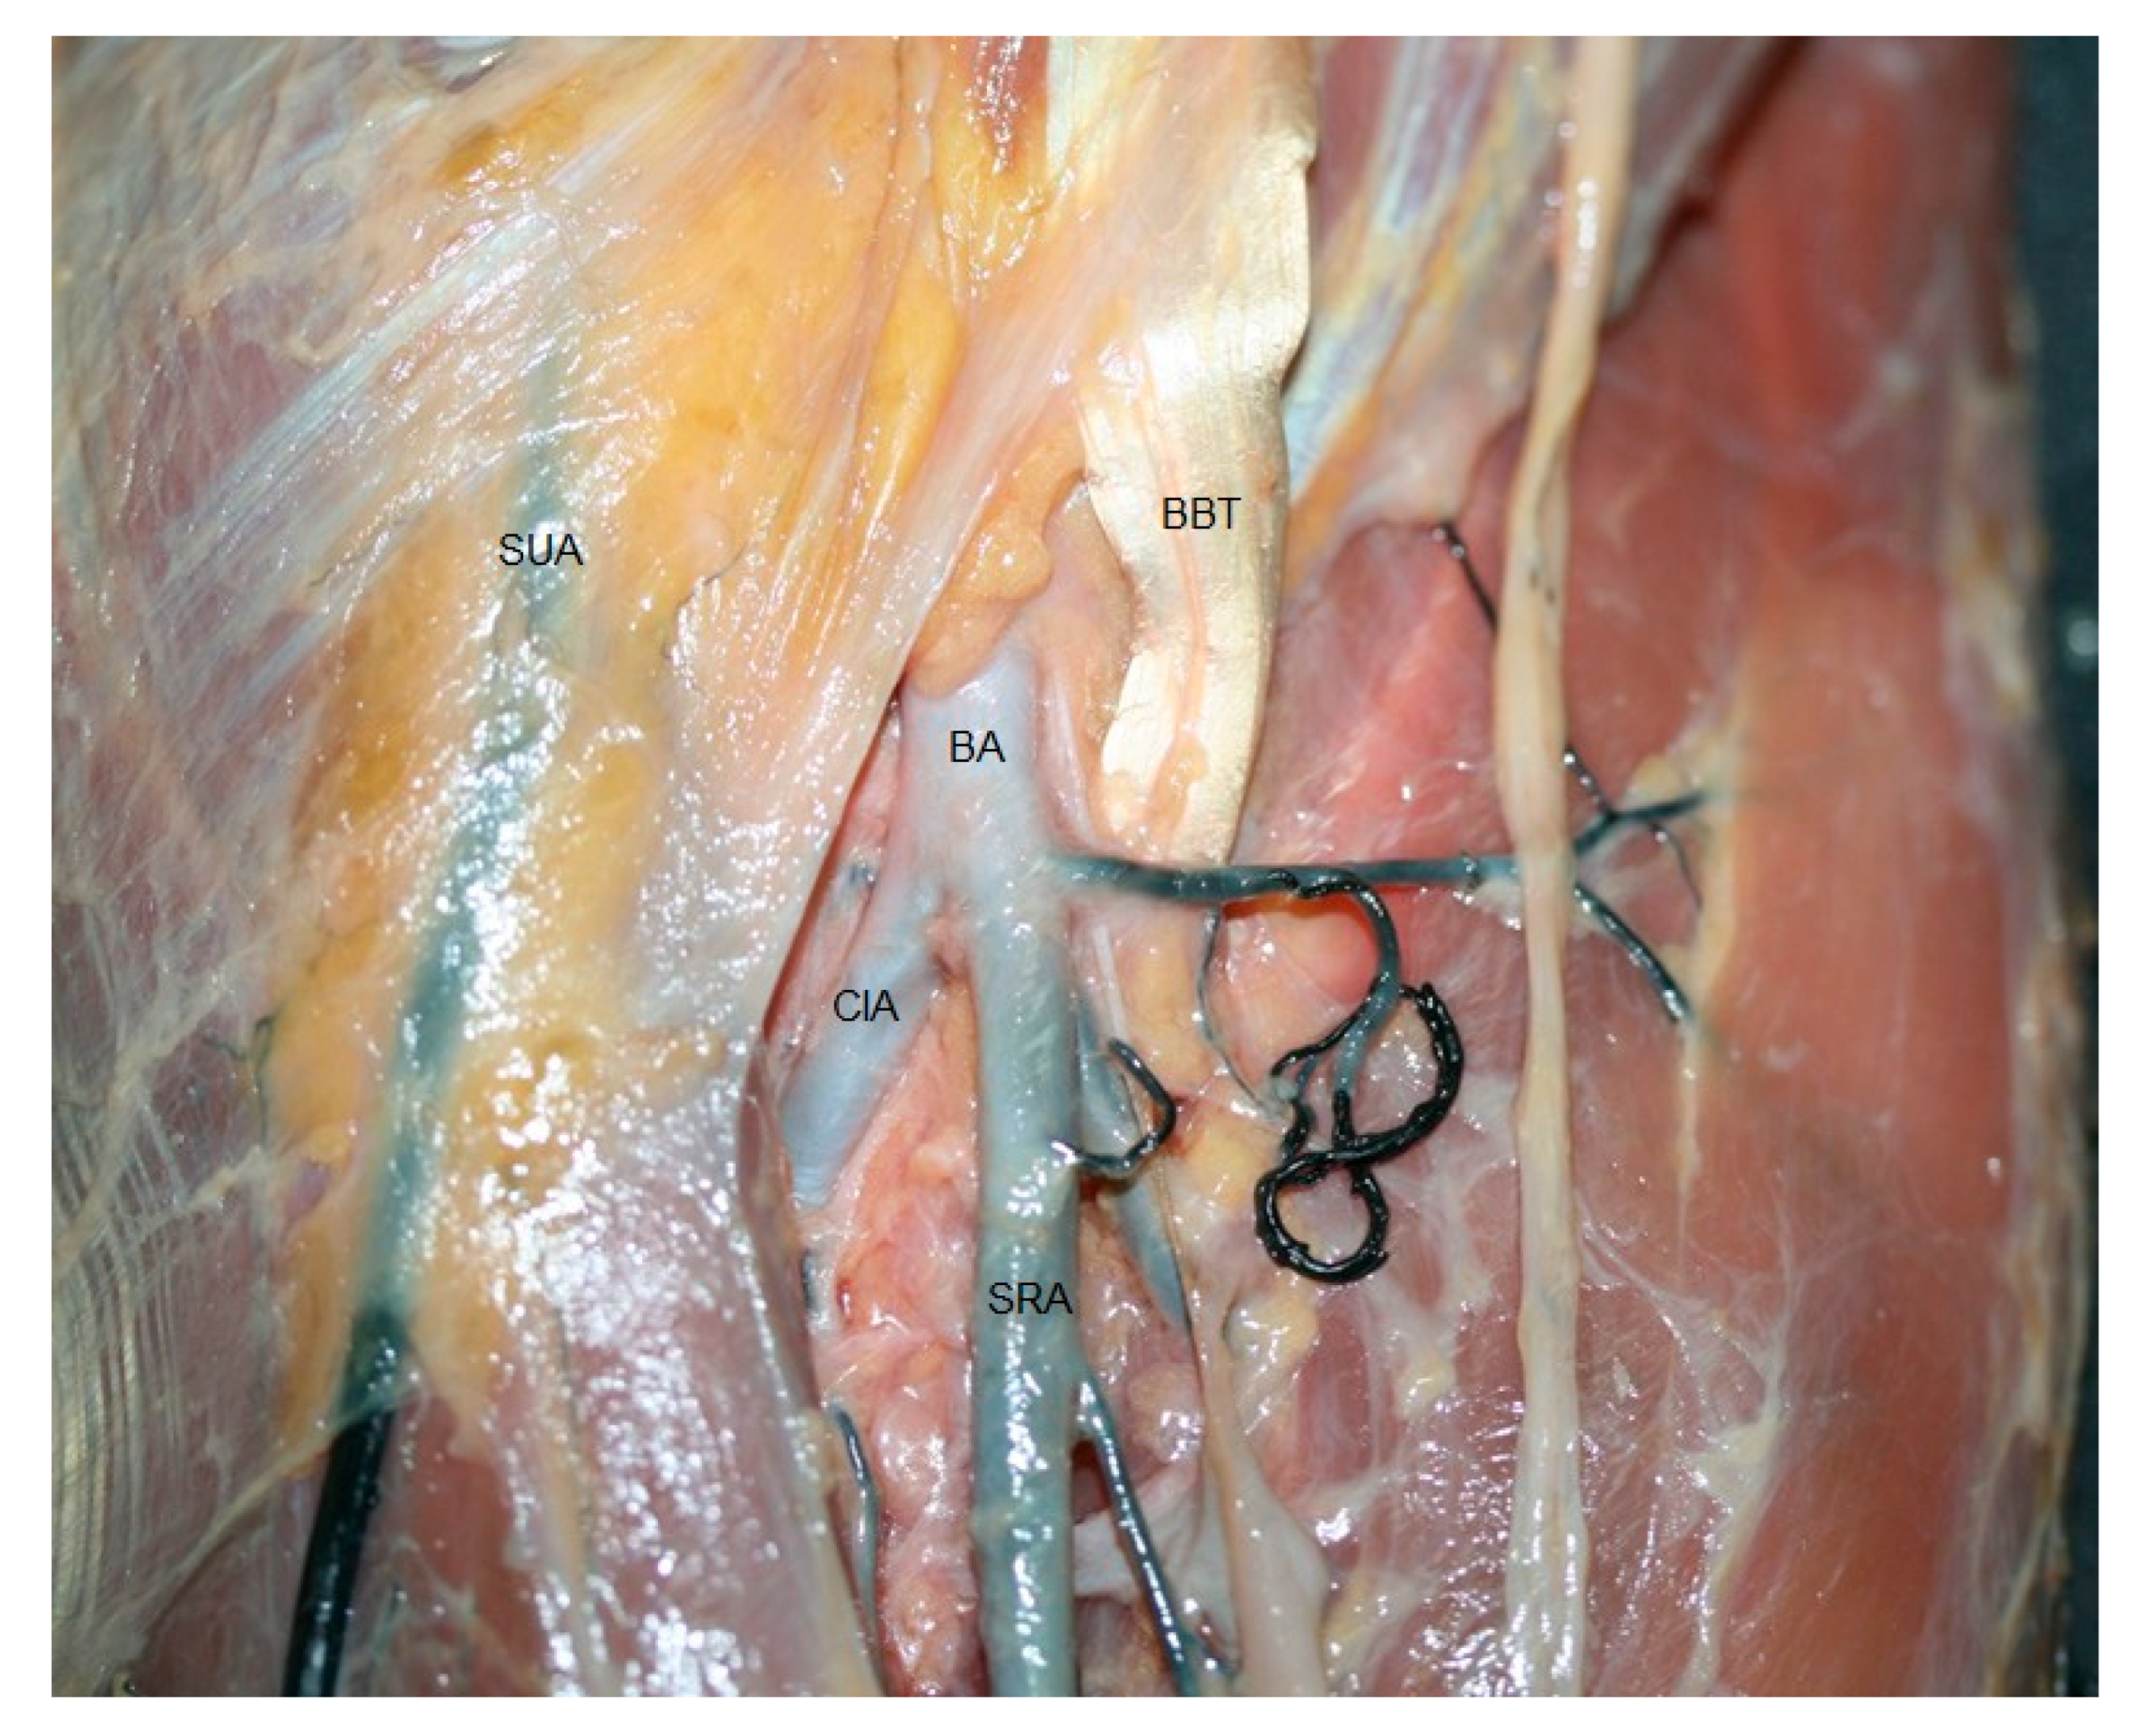

3.2. Anatomical Study